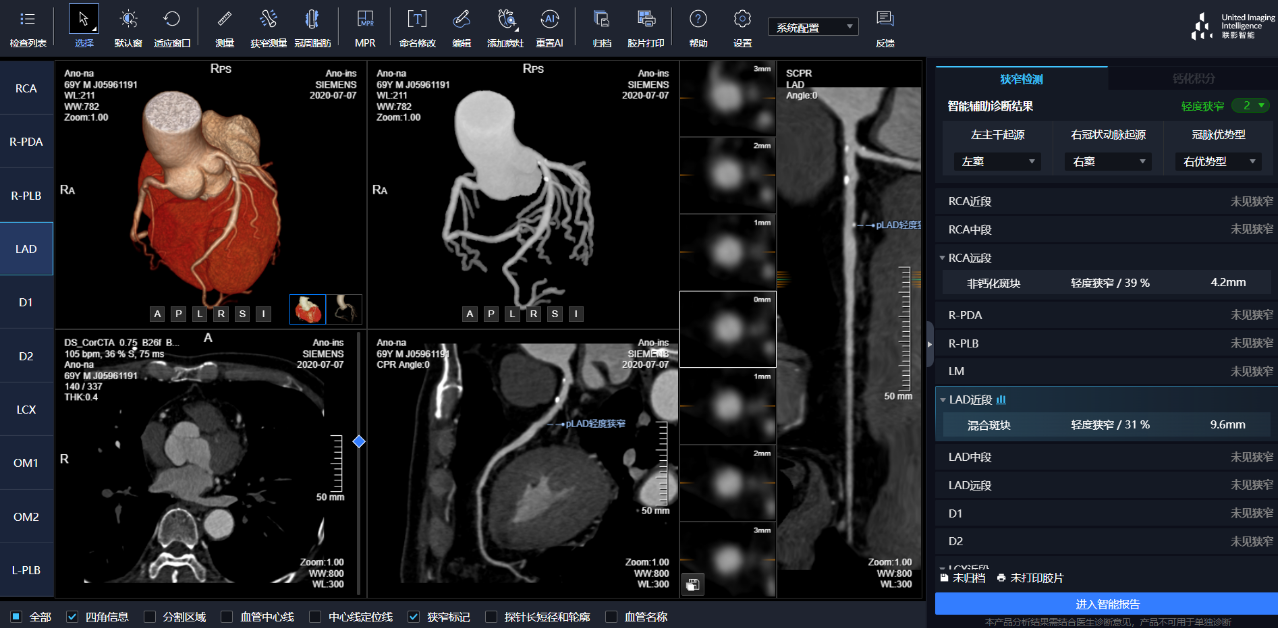

相較于傳統(tǒng)人工閱片,在聯(lián)影智能AI軟件的輔助下,640CT閱片的靈敏度和閱片效率均有顯著提升,對于細微骨折乃至于隱匿性骨折的判斷,準確度更高,極大地減少了漏診及誤診。

通過3D視圖可任意旋轉(zhuǎn)觀看血管全貌,AI秒級實時計算重建血管,可實現(xiàn)多維輔診包含:板塊定性定量分析、狹窄評估、心肌橋檢出、支架檢出、鈣化積分,全程AI關(guān)注心血管健康。